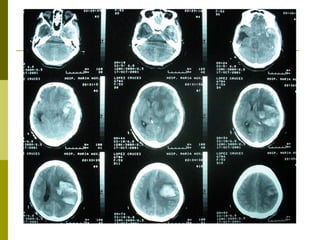

Clasificación Tomográfica del TEC según el National Traumatic Coma Data Bank (TCDB)  Grado, Tipo de lesión, TAC craneal I  Lesión difusa I  Sin patología visible en la TAC II  Lesión difusa II  Cisternas presentes con desplazamientos de la línea media de 0-5 mm y/o lesiones densas presentes. Sin lesiones de densidad alta o mixta > 25 cm3. Puede incluir fragmentos óseos y cuerpos extraños. III  Lesión difusa III (Swelling)  Cisternas comprimidas o ausentes con desplazamiento de la línea media de 0-5 mm. Sin lesiones de densidad alta o mixta > 25 cm3. IV  Lesión difusa IV (Shift)  Desplazamiento de la línea media > 5 mm. Sin lesiones de densidad alta o mixta > 25 cm3. V  Lesión focal evacuada  Cualquier lesión evacuada quirúrgicamente. VI  Lesión focal no evacuada  Lesión de densidad alta o mixta >25 cm3 no evacuada quirúrgicamente. Marshall L., Gautille R, Klauber M et al. The outcome of severe closed head injury. J. Neurosurg. 75 (S):528.1991.

Resultados Según la clasificación tomográfica del TEC, las lesiones  más frecuentes fueron:  Categoría VI TCDB: 10 - 28%.  Categoría V TCDB:  7 – 19% Categoría IV TCDB: 1 –3% Hematoma Extraaxial: 12 – 33%  Lesiones mixtas:  14 – 39%

Resultados Pacientes con TEC: Contusión Hemorrágica: 10 Contusión Hemorrágica + HSD: 9 HSD: 7 HED: 5 Contusión Hemorrágica + HED: 3 Contusión Hemorrágica + HSD + HED: 1 HED + HSA: 1

Clasificación Tomográfica delTEC según el National Traumatic Coma Data Bank (TCDB) Grado, Tipo de lesión, TAC craneal I Lesión difusa I Sin patología visible en la TAC II Lesión difusa II Cisternas presentes con desplazamientos de la línea media de 0-5 mm y/o lesiones densas presentes. Sin lesiones de densidad alta o mixta > 25 cm3. Puede incluir fragmentos óseos y cuerpos extraños. III Lesión difusa III (Swelling) Cisternas comprimidas o ausentes con desplazamiento de la línea media de 0-5 mm. Sin lesiones de densidad alta o mixta > 25 cm3. IV Lesión difusa IV (Shift) Desplazamiento de la línea media > 5 mm. Sin lesiones de densidad alta o mixta > 25 cm3. V Lesión focal evacuada Cualquier lesión evacuada quirúrgicamente. VI Lesión focal no evacuada Lesión de densidad alta o mixta >25 cm3 no evacuada quirúrgicamente. Marshall L., Gautille R, Klauber M et al. The outcome of severe closed head injury. J. Neurosurg. 75 (S):528.1991.

Resultados Según laclasificación tomográfica del TEC, las lesiones más frecuentes fueron: Categoría VI TCDB: 10 - 28%. Categoría V TCDB: 7 – 19% Categoría IV TCDB: 1 –3% Hematoma Extraaxial: 12 – 33% Lesiones mixtas: 14 – 39%

Resultados Pacientes conTEC: Contusión Hemorrágica: 10 Contusión Hemorrágica + HSD: 9 HSD: 7 HED: 5 Contusión Hemorrágica + HED: 3 Contusión Hemorrágica + HSD + HED: 1 HED + HSA: 1